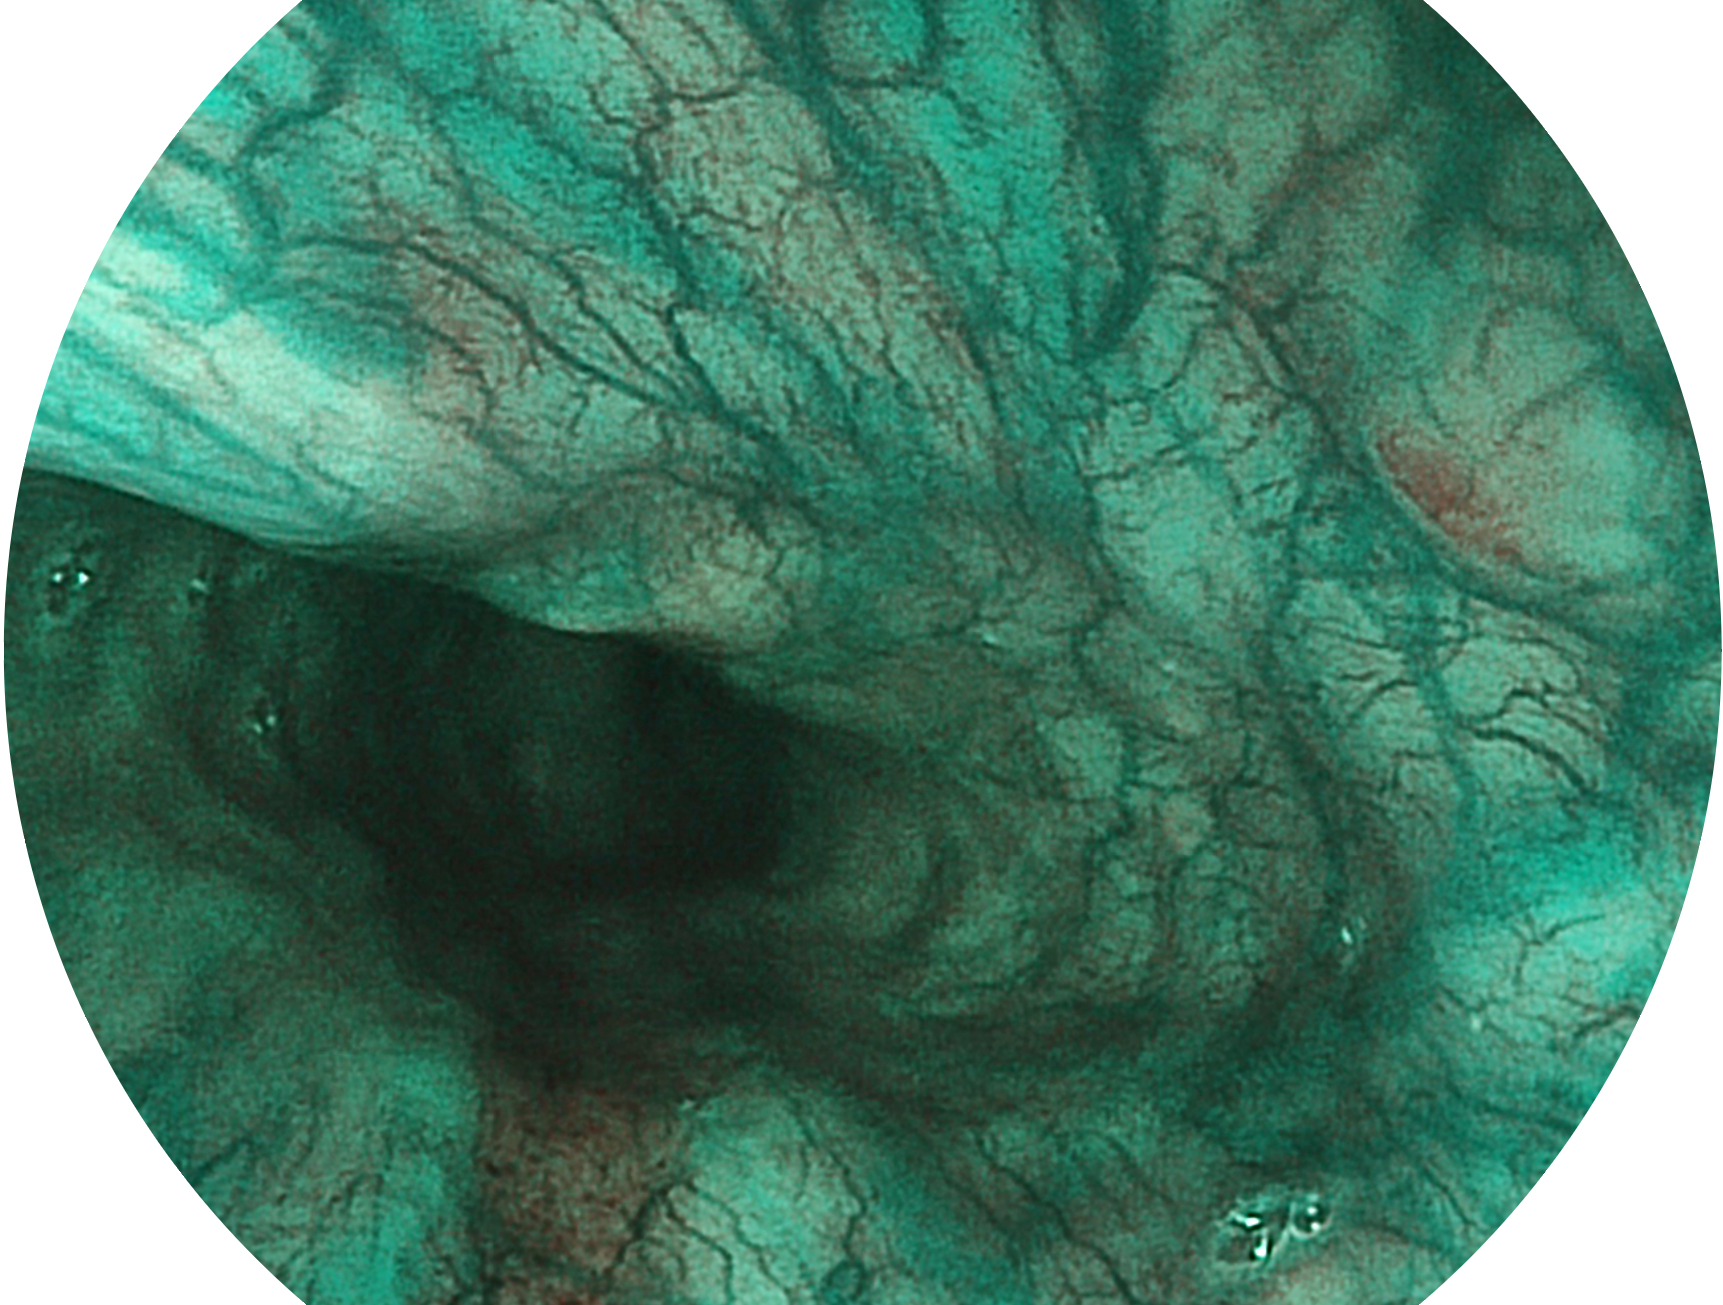

MILE米乐集团官网新开发的内镜染色技术,主要是基于多波长LED 光源的开发,VLS-55Q 四波长LED 光源是由四个不同颜色的LED光按照相应照明模式所规定的特定发光比例进行合束后形成,合束后形成的照明光的光谱由红光、绿光、蓝光及蓝紫光这四个不同的波段范围构成。具有更高光谱自由度,通过光谱比例的控制,实现了聚谱成像技术,英文全称为“Spectral Focused Imaging, SFI”,缩写为“SFI”和光电复合染色成像技术,英文全称为“Versatile Intelligent Staining Technology, VIST”,缩写为“VIST”。